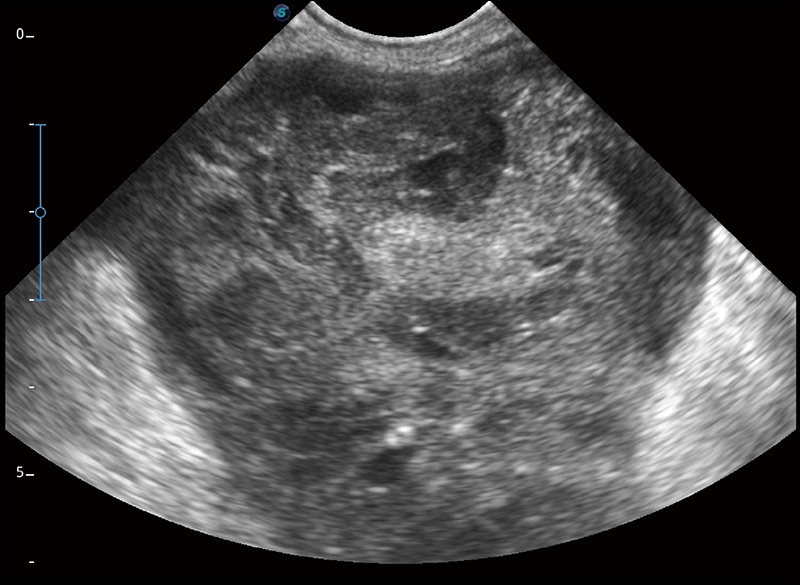

扩展成像

支持线阵和凸阵探头,一键操作即可获得更宽的图像视野